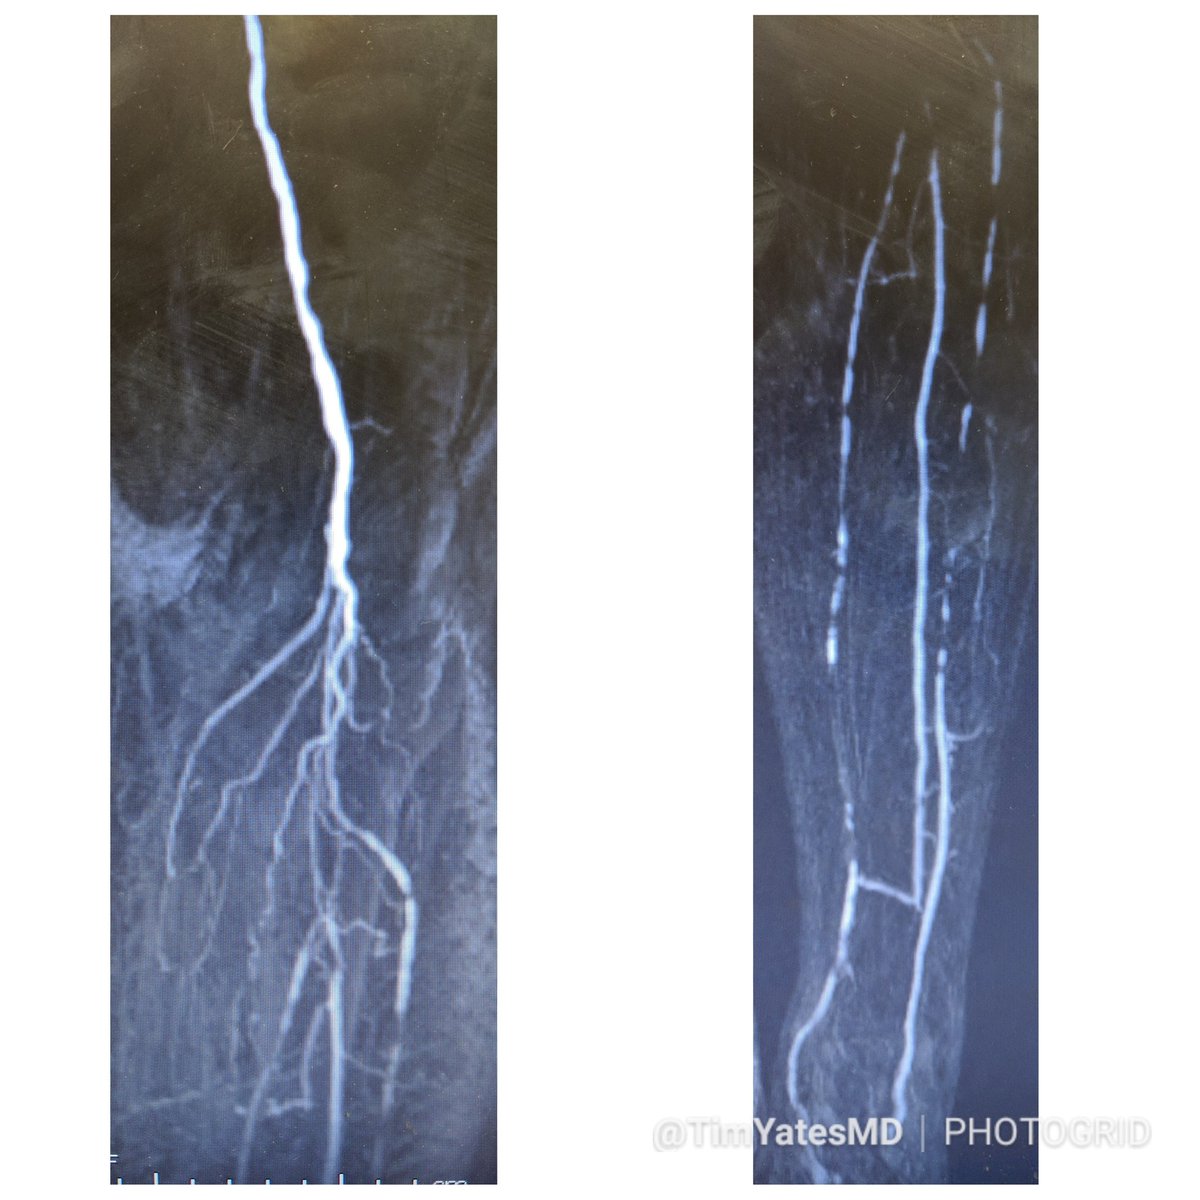

MRA can be MORE sensitive to tibial occlusive disease than DSA. MRA helped plan approach due to knowledge of hibernating AT and peroneal lumen. Successful antegrade luminal recan for #CLI #CLIfighters #mylegmylife @FadiSaab17 @Mustapja @roblookstein @DrBTKatzen @BOlivieriMD